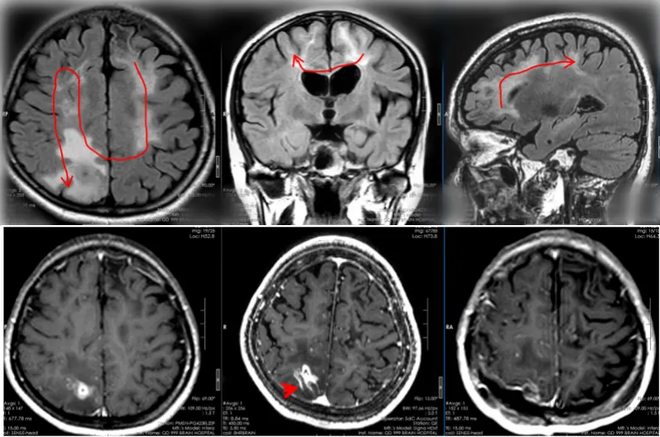

Bệnh nhân nữ, 28 tuổi ở Trung Quốc lần đầu lên cơn động kinh nặng "đột ngột ngã xuống đất, chân tay co giật và sùi bọt mép" cách đây 4 năm. Ban đầu, mặc dù kiểm tra cho thấy những bất thường ở não nhưng các bác sĩ vẫn chưa thể chẩn đoán được nguyên nhân cụ thể. Cùng lúc đó, người này bắt đầu cảm thấy chân tay phải yếu đi.

Sau đó một thời gian, cô gái được phán đoán mắc bệnh sán não. Vì bào tử sống nằm ở vùng chức năng nội sọ nên phẫu thuật có thể gây tổn thương và làm nặng thêm tình trạng rối loạn chức năng, do đó bệnh nhân được chỉ định theo dõi thêm.

Trong hai năm qua, bệnh nhân này vẫn kiên trì dùng thuốc và khám sức khỏe định kỳ, không còn bị động kinh nữa. Tuy nhiên, chân phải của cô tiếp tục yếu và trí nhớ cũng suy giảm. Vào ngày 20/4 vừa qua, các bác sĩ cuối cùng đã phát hiện con giun ký sinh di chuyển đến vùng không còn chức năng của thùy đỉnh bên phải của bệnh nhân.

Chớp lấy thời cơ, 3 ngày sau, bệnh nhân được thực hiện ca phẫu thuật mở hộp sọ cho bệnh nhân, không chỉ "bắt" thành công một con giun dài 20cm còn sống , mà còn loại bỏ được "tổ giun" (u hạt viêm).